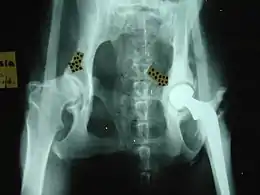

Orthopedic surgery

Common orthopedic surgeries in animals include:

- For hip dysplasia:

- Femoral head osteotomy

- Triple pelvic osteotomy

- Hip replacement